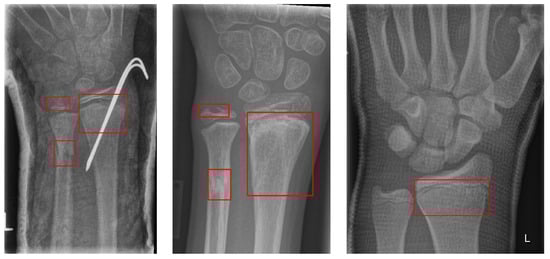

3. Materials

The musculoskeletal radiographs (MURA) dataset is a large compilation of musculoskeletal radiographs for seven upper extremities: the elbow, finger, forearm, hand, humerus, shoulder, and wrist. These were obtained from 12,173 patients at Stanford Hospital between 2001 and 2012 and were manually classified as normal or abnormal by Stanford Hospital radiologists. The total number of images is 40,561, of which 9752 (negative: 5765, positive: 3987) are wrist images. In addition, the validation dataset comprises 659 images (negative: 364, positive: 259). Stanford University has released the MURA dataset for research purposes. Figure 1 provides examples from the positive dataset.

Figure 1. Positive MURA dataset: (a) elbow, (b) finger, (c) forearm, (d) hand, (e) humerus, (f) shoulder, (g) wrist, (h) wrist.